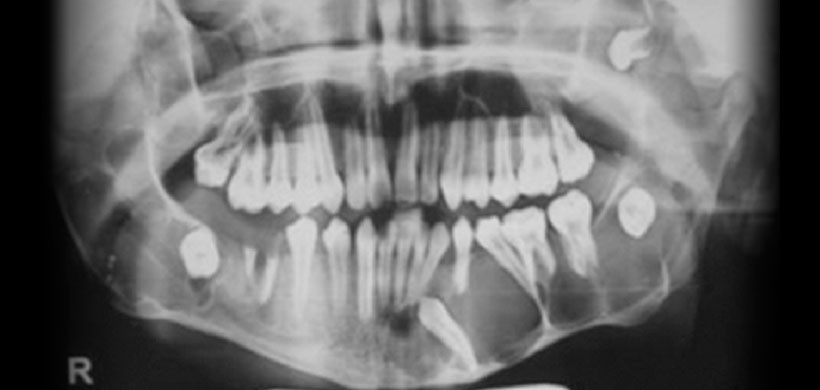

Fig 3. Radiografía panorámica, muestra múltiples lesiones radiolucidas de limites definidos y bordes corticalizados, localizado en cuerpo, y rama mandibular bilateral y region posterior del maxilar superior.